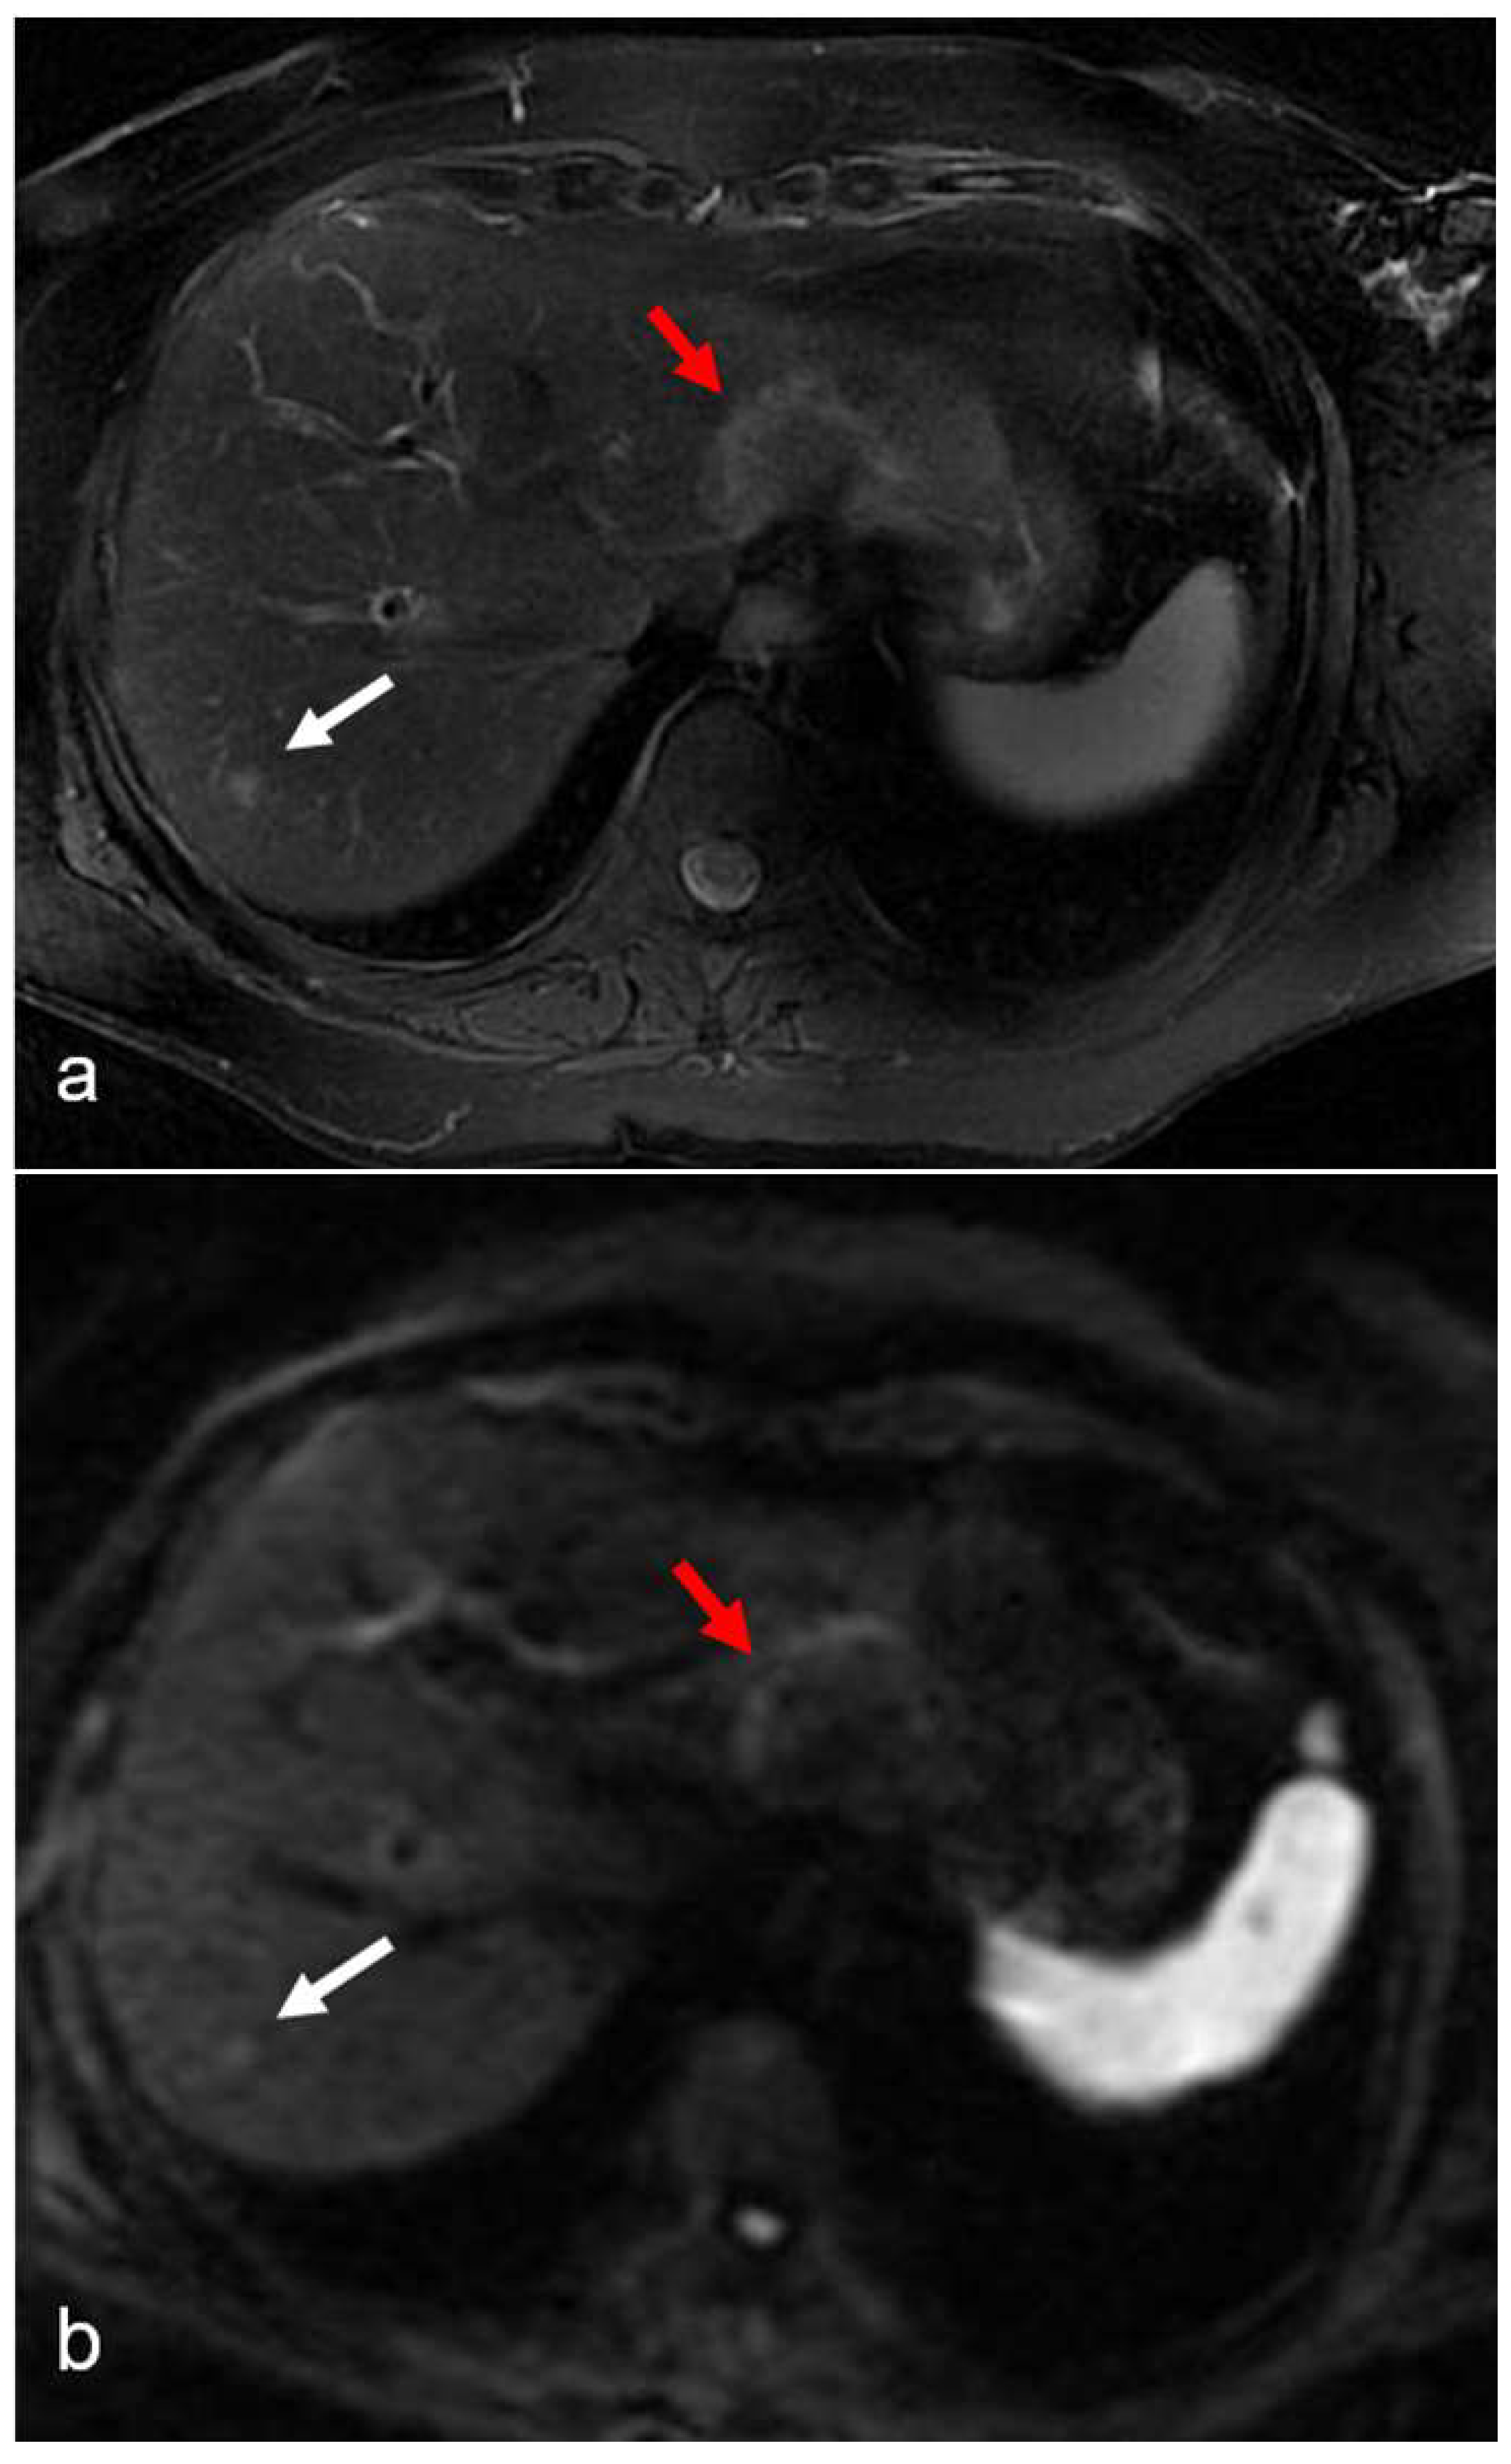

Focal Chemotherapy-Induced Hepatopathy

- Han, N.Y.; Park, B.J.; Sung, D.J.; Kim, M.J.; Cho, S.B.; Lee, C.H.; Jang, Y.J.; Kim, S.Y.; Kim, D.S.; Um, S.H.; et al. Chemotherapy-induced focal hepatopathy in patients with gastrointestinal malignancy: Gadoxetic acid–enhanced and diffusion-weighted MR imaging with clinical-pathologic correlation. Radiology 2014, 271, 416–425. [Google Scholar] [CrossRef]

- Choi, J.H.; Won, Y.W.; Kim, H.S.; Oh, Y.H.; Lim, S.; Kim, H.J. Oxaliplatin-induced sinusoidal obstruction syndrome mimicking metastatic colon cancer in the liver. Oncol. Lett. 2016, 11, 2861–2864. [Google Scholar] [CrossRef]

- Alexandrino, H.; Oliveira, D.; Cipriano, M.A.; Ferreira, L.; Tralhão, J.G. Oxaliplatin toxicity presenting as a liver nodule—Case report. BMC Cancer 2015, 15, 247. [Google Scholar] [CrossRef][Green Version]

- Uchino, K.; Fujisawa, M.; Watanabe, T.; Endo, Y.; Nobuhisa, T.; Matsumoto, Y.; Kai, K.; Sato, S.; Notohara, K.; Matsukawa, A. Oxaliplatin-induced liver injury mimicking metastatic tumor on images: A case report. Jpn. J. Clin. Oncol. 2013, 43, 1034–1038. [Google Scholar] [CrossRef]